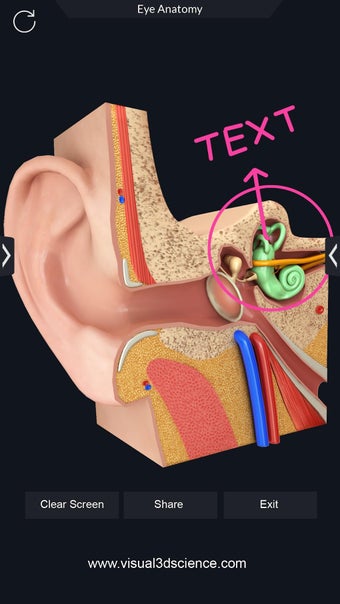

Una aplicación gratuita para Android, creada por Visual 3D Science.

Puedes seleccionar cada parte del cuerpo por separado para ver su nombre o leer información relacionada. Puedes ocultar y mostrar cada parte del cuerpo, así como rotar 360° alrededor de un modelo 3D altamente realista. Puedes dibujar en la pantalla o compartir capturas de pantalla con tus amigos. Puedes encontrar la definición de cada parte del cuerpo y su anatomía.